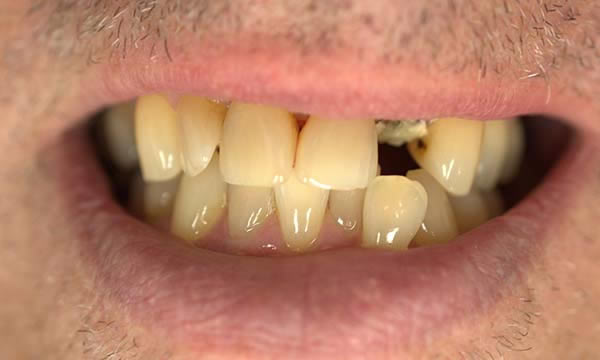

Case F

This gentleman came to see me after his crown decorated. He was fed up with being called a pirate by his grandchildren and decided to do something about the gap.

Due to an absence of infection and an atraumatic extraction, the removal of the tooth was followed by immediate implant placement. The implant was restored with an Atlantis abutment and bonded crown.

Before Treatment